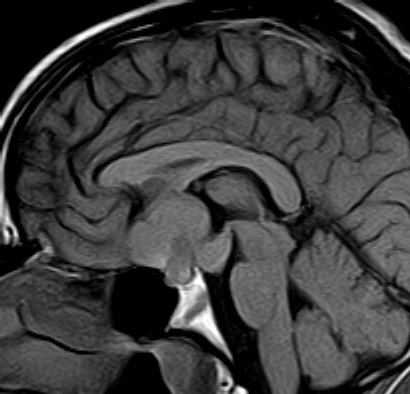

December 2005 - Craniopharyngioma

There is evidence of a lobulated extra-axial mass lesion in the suprasellar cistern. The lesion is predominantly hyperintense on the T1W images and heterogeneously hyperintense on the T2W and FLAIR images. The optic chiasm, proximal optic nerves and the pituitary stalk cannot be identified separately from this lesion. However, the pituitary gland is well identified.

Craniopharyngiomas are epithelially derived neoplasms that usually occur in the suprasellar cistern. Occasionally they occur in the sella or in the third ventricle.  They constitute approximately 3% of all intracranial tumors and show no sex predilection. Craniopharyngiomas are hormonally inactive lesions. 50% of these lesions occur in childhood or adolescence, with a peak incidence between 5 and 10 years of age. A second smaller peak is seen in the sixth decade. Patients may present with headaches and/or visual disturbances. The lesions usually exhibit a heterogeneous appearance with presence of a cystic and/or solid component. It may be hyperintense on both T1W and T2W images. The lesions may encase nearby cerebral vasculature. The solid portion may be calcified. On contrast the solid portion usually enhances.